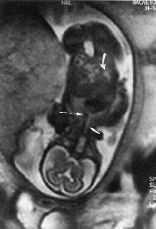

La RM confirmó todos los hallazgos de los US como se detalla en la tabla 2, permitiendo además descubrir otros no detectados por ecografía. En el caso número 3, higroma quístico en gestación de 21 semanas, la RM permitió visualizar edema del dorso de las manos, de los pies y de la región pretibial (Fig. 1), no visualizados mediante ecografía, hallazgos muy sugestivos de Síndrome Turner confirmándose en el estudio del cariotipo fetal. En el caso número 4, hidrocefalia y pies equinovaros, la RM visualizo además una hipoplasia del cerebelo (Fig. 2), confirmada en la necropsia. En el caso número 5, gestación gemelar y presencia de hydrops fetal severo de uno de los fetos, a pesar de un estudio incompleto de la RM por un síndrome supino hipotensor materno, puso de manifiesto una alteración en la imagen del líquido amniótico del segundo feto, hallazgo sugestivo de sangrado o presencia de meconio. En el caso número 8, la RM permitió el diagnóstico de hernia diafragmática al visualizar los diafragmas y la disposición de los órganos toracoabdominales (Fig. 3). El estudio postnatal confirmó el diagnóstico. En un oligoamnios severo por RPM a las 33 semanas, caso número 9, el examen mediante US detectó un mielomeningocele lumbar, hallazgos confirmados por la RM, permitiendo un examen detallado de la anatomía fetal a pesar de la ausencia de líquido amniótico y la detección de un síndrome de Arnold Chiari tipo II no detectado por ecografía. Por último en el caso número 13, gestación de 33 semanas con desplazamiento cardíaco, la RM evidenció un arco aórtico derecho (Fig. 4), no visualizado por US, sugestivo de cardiopatía, estando pendiente de estudio postnatal al no haber finalizado aún el embarazo.

Figura 3.Hernia diafragmtica izquierda en una gestacin de 27 semanas. Imagen coronal fetal. Elevacin del diafragma izquierdo (flecha). Diafragma derecho (punta de flecha). Estmago (flecha curva).

Figura 4.Arco artico derecho (flecha larga) en una gestacin de 22 semanas. Imagen coronal fetal. Trquea (flecha corta). Estmago (flecha curva).